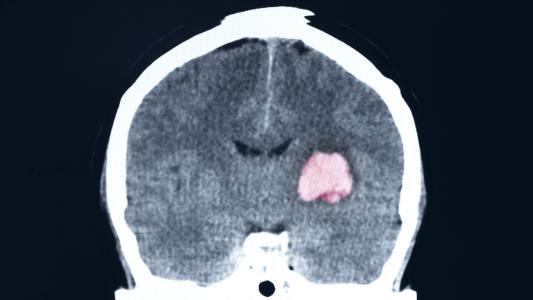

A modified herpes virus can fight brain cancer in children